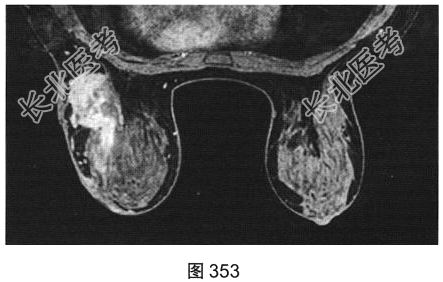

- [材料题] 患者女性,28岁,哺乳后3个月出现左乳肿胀、疼痛,患者无发热。既往体健。查体:左乳皮肤变红、皮温升高,外象限可触及一肿块。

- 简答题3、[提示]患者行乳腺MRI检查,如图351~图356所示。乳腺MRI检查的阳性影像学表现有?